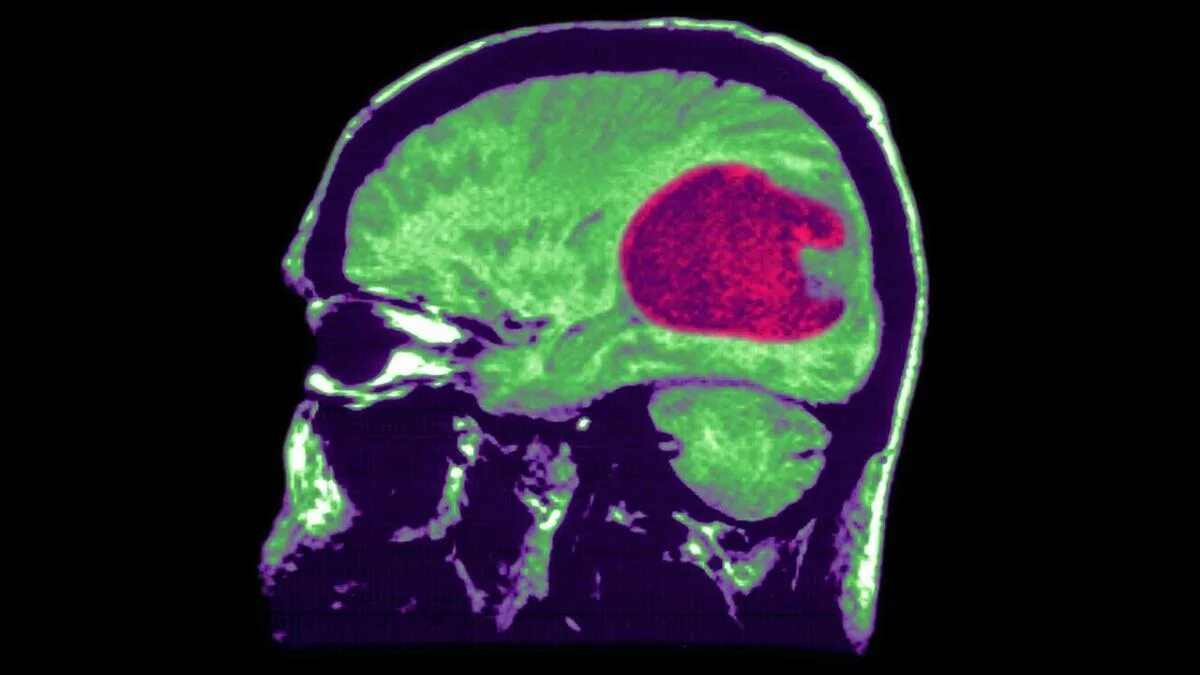

Отек мозга метастазы